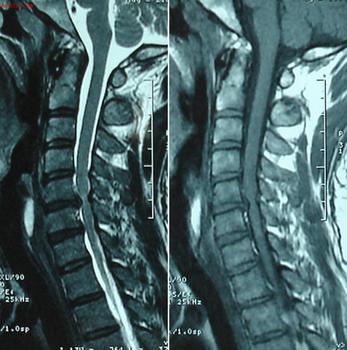

蒙兴文主任介绍说:强直性脊柱炎在临床上进行诊断的方法主要是看病人症状配合放射线影像结果,综合分析才能对疾病进行确诊。一般强直早期的患者都会有骶髂关节的病变,但是这种病变在外观上很难得出结果。但是从X线影像上便能看出骶髂关节缝隙处变化,这是判断是否为强直的重要依据。强直性脊柱炎的判断需要综合分析,下面我们来看判断是否强直需要考虑哪些。